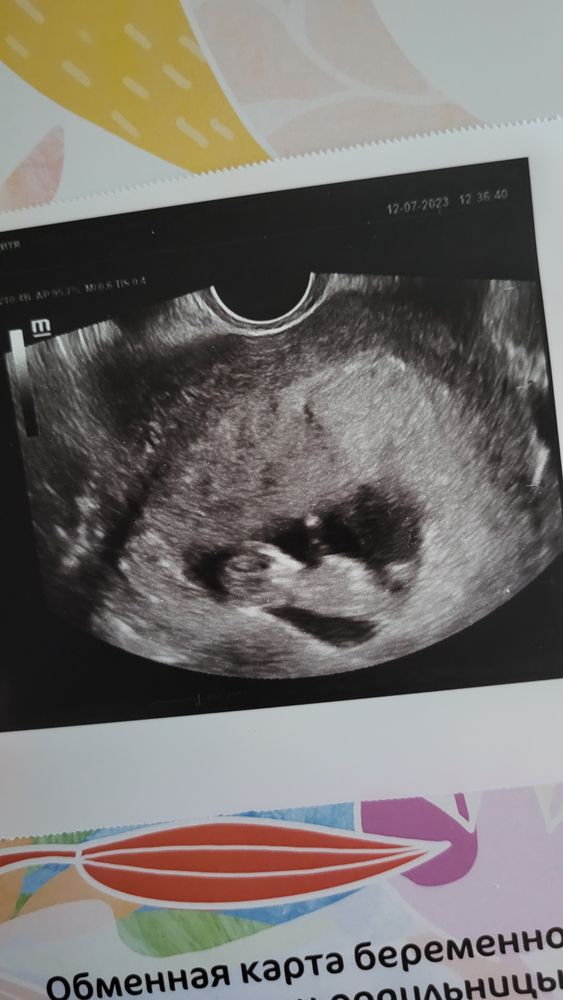

Как они быстро растут! Уже прям человек человек!

Ого, уже 10 неделек у вас👍